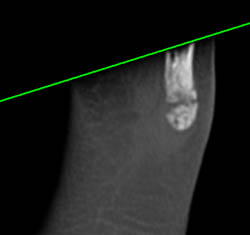

Nice CTA at Elbow